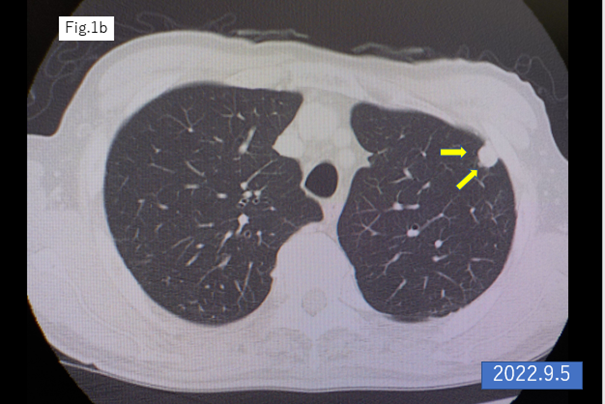

An 87-year-old male underwent laparoscopic left hemicolectomy with a diagnosis of adenocarcinoma of the descending colon in December 2021. Lung metastasis was found in the left upper lobe 6 months postoperatively, and it increased in size after 9 months from the surgery (Figures 1a,b). The patient began S-1 plus oxaliplatin (SOX) treatment with first-line chemotherapy consisting of oral S-1 (a mixed drug of tegafur, gimeracil, and oteracil potassium) at a dose of 50 mg twice daily for 2 weeks following by 1-week off schedule, and intravenous oxaliplatin (100 mg/m2) given on day 1 of a 3-week cycle [2,3], was started in October 2022.The lung metastasis was shrinking within 23 cycles of SOX therapy (Figures 1c–f). The 24th cycle of SOX (only oxaliplatin) was administrated in April 2024, the catheter of venous chemotherapy line of right forearm was removed after finishing the infusion, however bleeding did not stop. The patient had vomiting, chill and pale face, and was transferred to the intensive care unit. The platelet count was rapidly dropped into 2,000/μl from 131,000/μl (pretreatment) within 7 hours and hemoglobin levels decreased from 10.9 g/dl to 8.9 g/dl in the same period, furthermore, dropped into 6.2 g/dl in next 24 hours. Disseminated intravascular coagulation (DIC) score was 8 points, and platelet-associated IgG (PA-IgG) was significantly high (204.0 ng/107 cells; normal < 30>.

Figure 1: CT scan of the lung